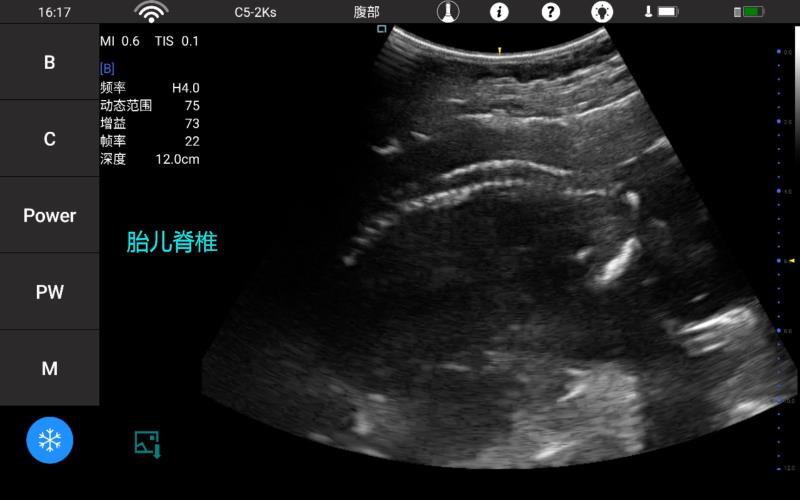

• 大凸

腹部

肾脏

妇科产科

心脏

肺等